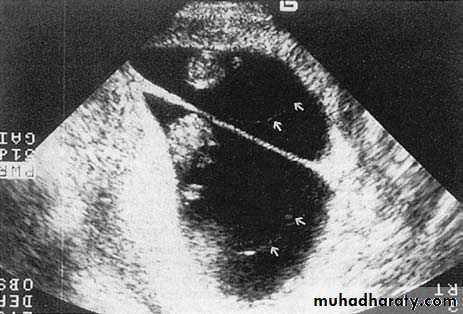

Ultrasound and invasive procedures

Ultrasound is used to guide invasive diagnostic procedures such as amniocentesis, chorion villus sampling and cordocentesis, and therapeutic procedures such as the insertion of fetal bladder shunts or chest drains.If fetoscopy is performed, the endoscope is inserted under ultrasound guidance.

precision to the appropriate place.